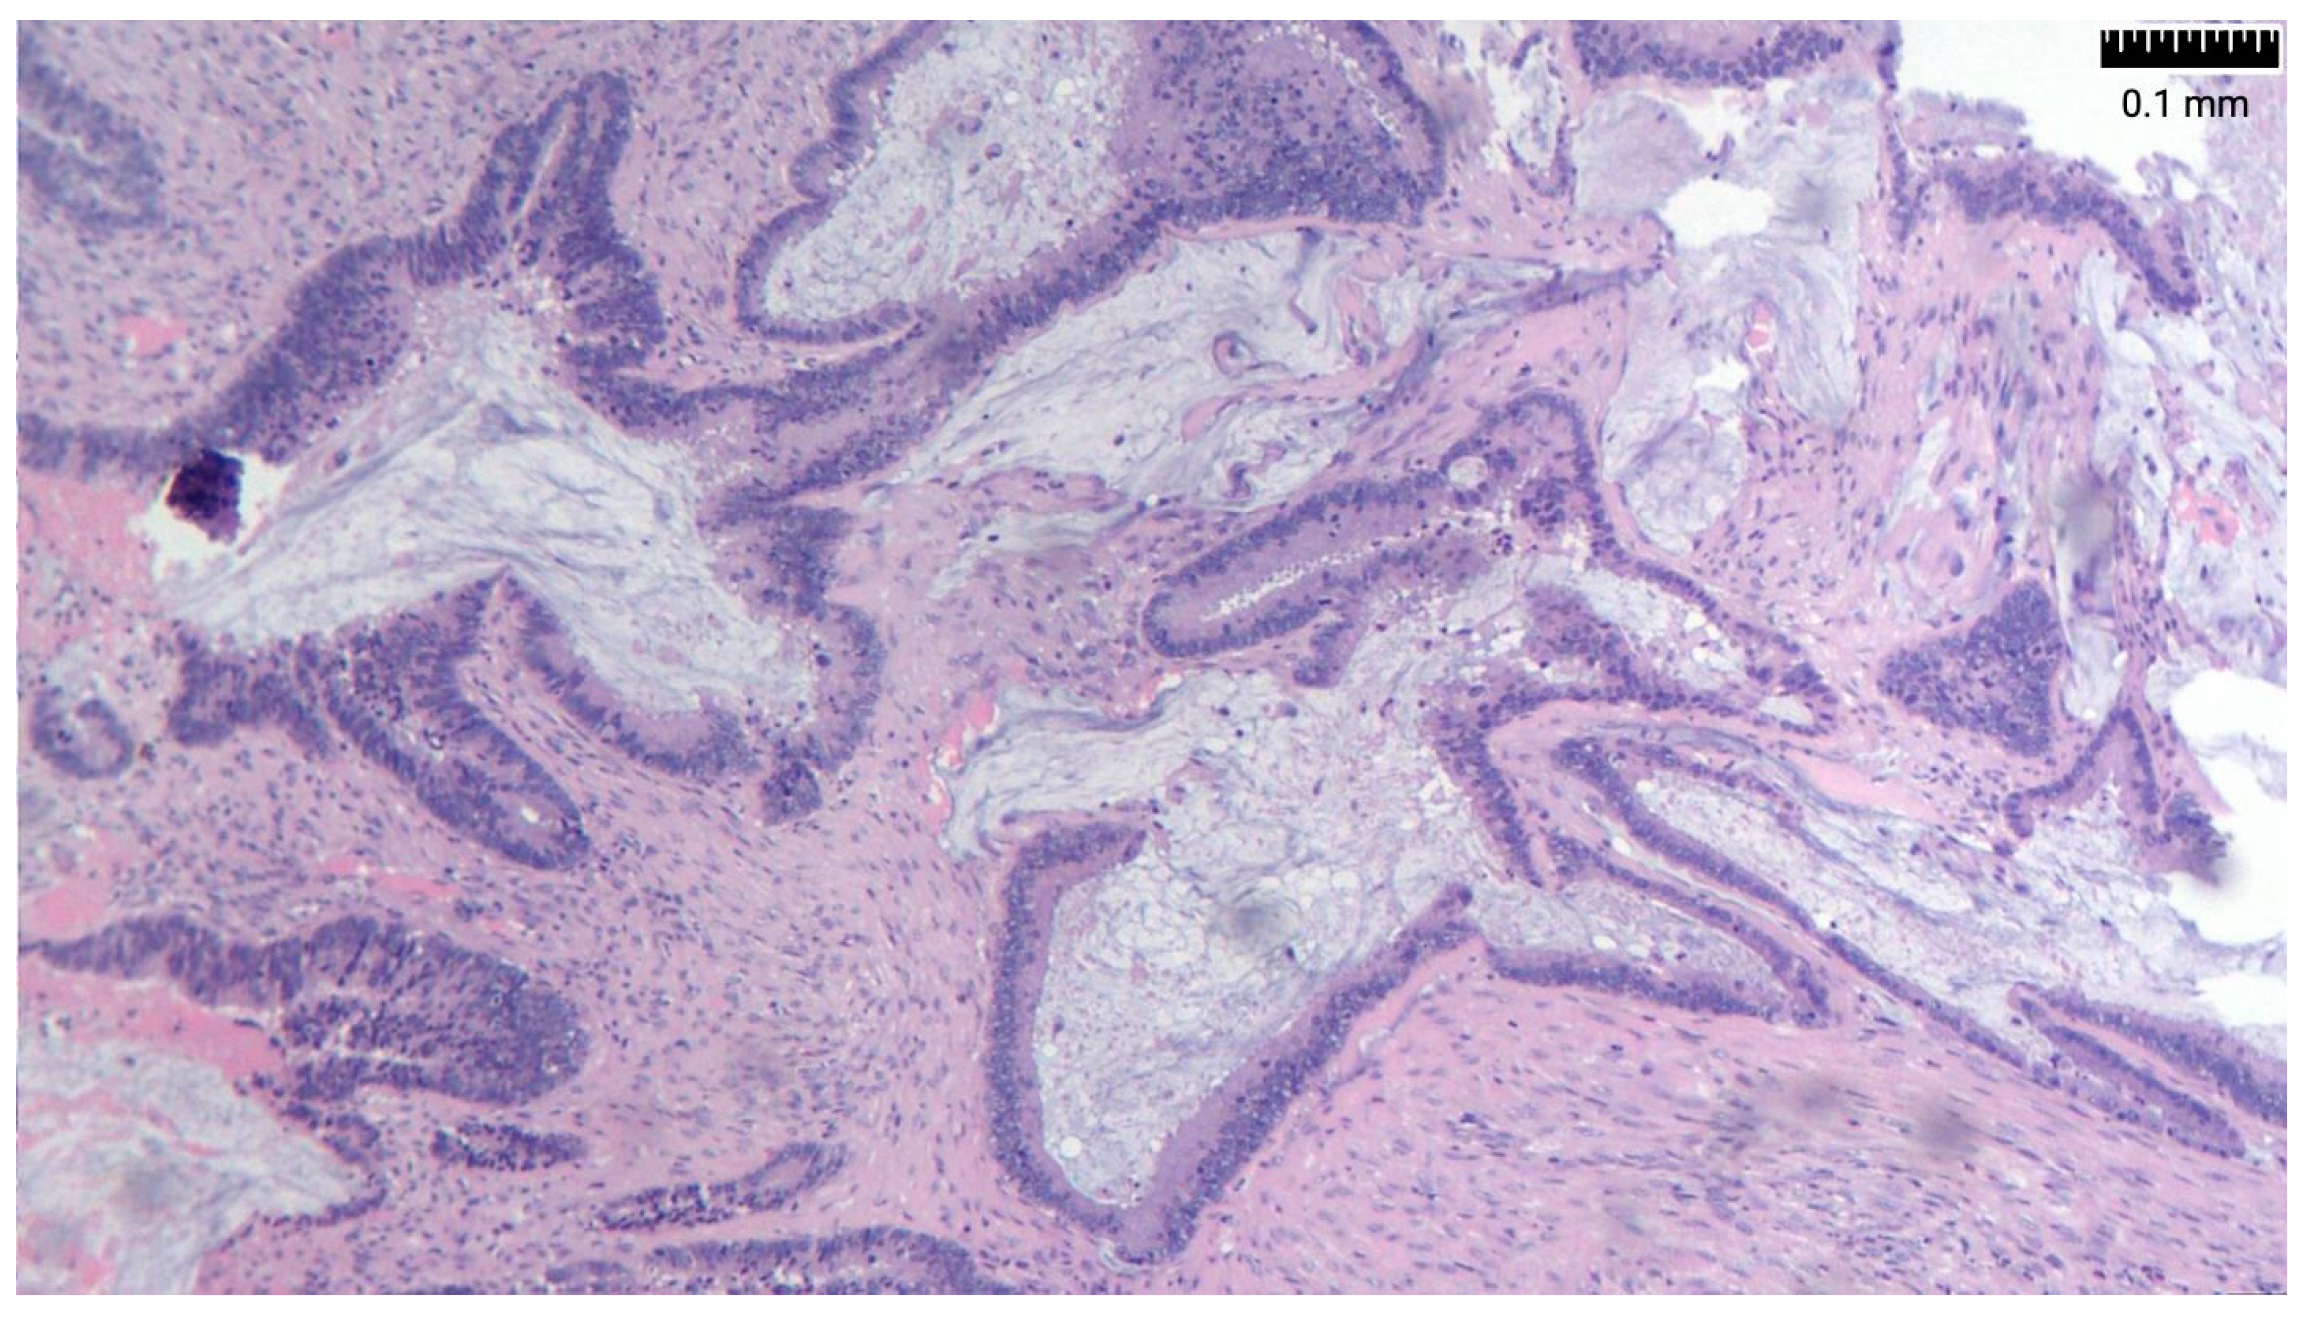

Researchers have suggested the overexpression of MUC2 as a molecular marker for PP of intestinal origin. Immunohistochemically, appendiceal tumors also express CK20, CEA, and CDX2 and are usually negative for CK7 and CA 125. There are also reports of loss of expression of the mismatch repair genes MLH-1 and PMS-2 (Figure 3 and Figure 4) [26,27] (Table 2).

Figure 3. MLH-1: positive nuclear staining in tumor cell.

Figure 4. PMS-2: positive nuclear staining in tumor cell.